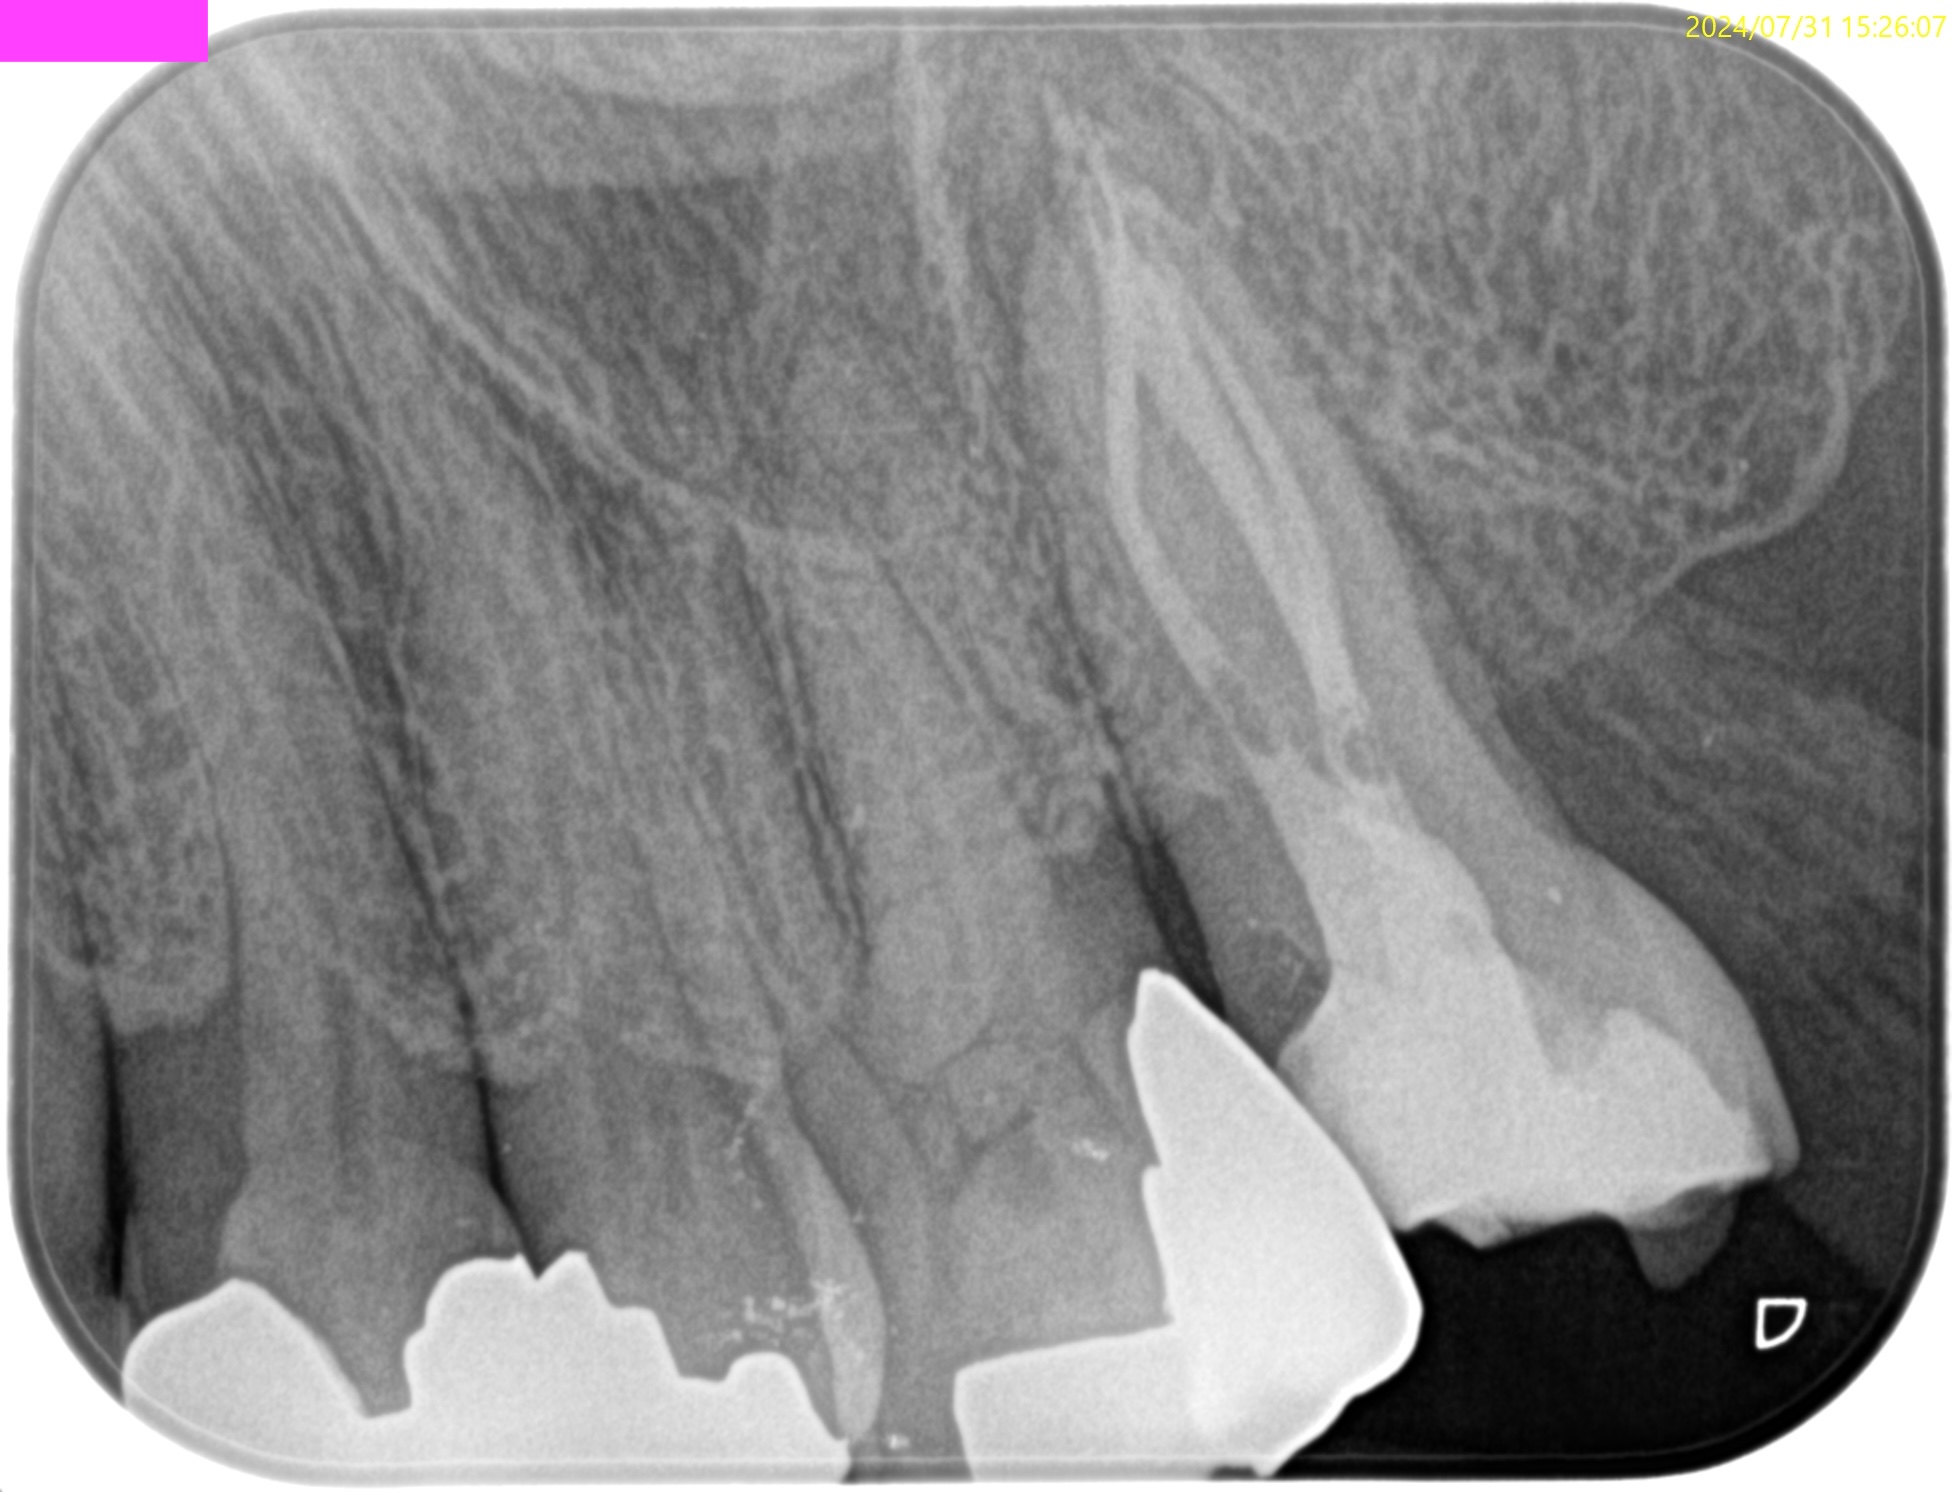

#15 RCT(2024.7.31)

術後にPA, CBCTを撮影した。

MB

DB

P